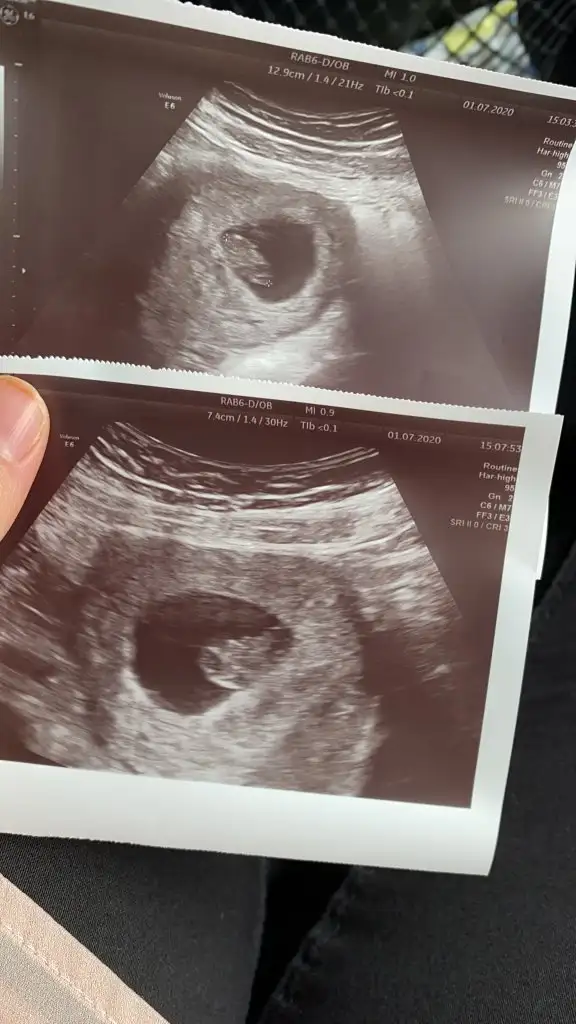

13+5 de nub biter ama kıza benzettim yani sagdakiniKizlar size iki tane resim biri kizima biri ogluma ait sizce hangisi kiz hangisi erkekEki Görüntüle 2657161 Eki Görüntüle 2657162

Canım çok net değil emin olamadım sanki sanki erkek olursa 13 hafta paylaş cnmKuzum buna da bakabilir misin ?

En iyi 11 12 13 şimdilik erkek kese konumuAnlayanlar bunada bir yorum yapabilir misiniz acaba